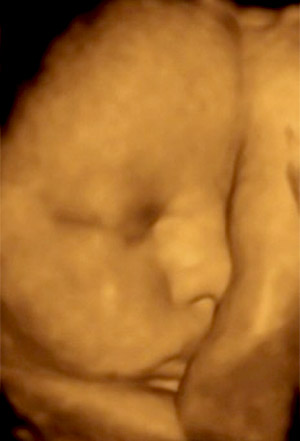

By the ninth month, the average baby is about 47 cm (18.6 inches) and weighs 2.6 kilograms (5.8 pounds). The brain has been developing rapidly and the lungs are nearly fully developed. The baby continues putting on half a pound a week until about week 37, at which weight gain slows down. A pregnancy is considered 'at term' once 37 weeks has been completed -- baby is due to arrive anytime! You may feel Braxton Hicks contractions, which get your body ready for labor. The baby's head is usually positioned down into the pelvis by now -- called lightening -- which can cause some pressure on the pelvic floor.